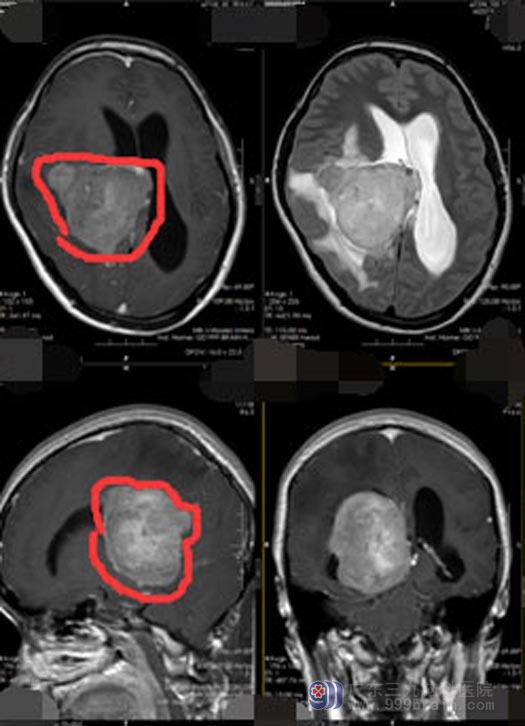

广东三九脑科医院副院长、神经外五科主任鲁明接诊后进行了仔细阅片,头颅MR检查显示“右侧侧脑室三角区内团块状长T1稍长T2异常信号FLAIR系列呈现高信号,增强好明显强度,范围约53.2mm×65.6mm×66.3mm,周围示片状水肿信号影,邻近脑组织受压,慕上脑室系统扩大,中线结构轻度左偏,颅内软脑膜强化略明显,矢状位矢小脑扁桃体下缘变尖,垂体未见异常,各副鼻窦腔清亮,所见范围内鼻咽部形态,信号未见明显异常”。初步诊断:1、右侧侧脑室三角区占位病变,考虑脑膜瘤可能性大,占位效果明显;2、幕上梗阻性脑积水;3、小脑扁桃体下疝,右侧大脑镰下疝。